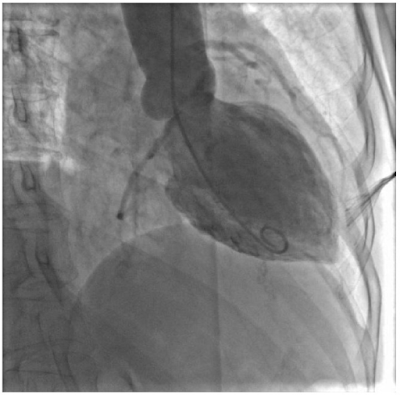

На наступному малюнку Ви можете спостерігати рентгенограму лівого шлуночка серця в пацієнта з синдромом Такоцубо. Це рідкісне набуте захворювання, основним проявом якого є запалення частини серцевого м’яза з наступним порушенням його скоротливості. Основний метод діагностики — вентрикулографія. Стрілкою відмічена ділянка серцевого м’язу, яка добре скорочується. Інші частини лівого шлуночка серця не беруть участь у скороченні. Серце набуває форми “медузи”.